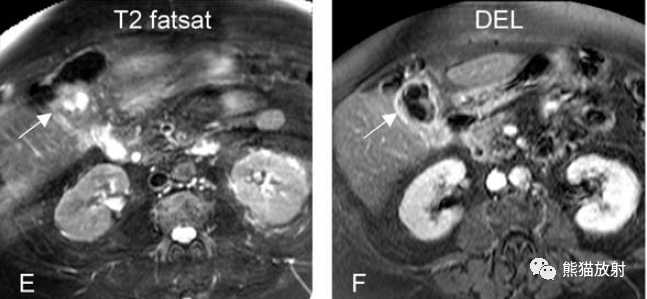

另一例膽囊癌,T2WI及增強(qiáng)延遲期顯示膽囊壁不均勻增厚并明顯強(qiáng)化。